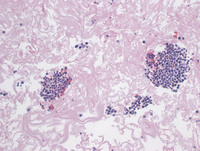

Figure 4: H&E in Primary Effusion Lymphoma

The H&E image of the cell block shows clusters of large atypical plasmacytic cells.